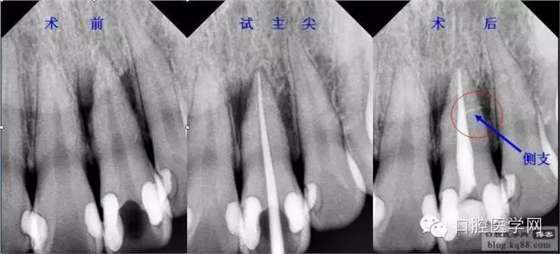

現(xiàn)代的根管充填技術(shù)是通過向預(yù)備好的根管充入牙膠和封閉劑達到高度的致密性、良好的錐度、精確的長度、所有根管空間(包括分支、側(cè)支、峽部、交通支)的完善封填。

試好后的主尖經(jīng)X片評價合適后要放入2.5%的次氯酸鈉中消毒備用,一般3分鐘就可以達到消毒標準,然后充填時用氣槍吹干,不能用棉球或紗布擦。